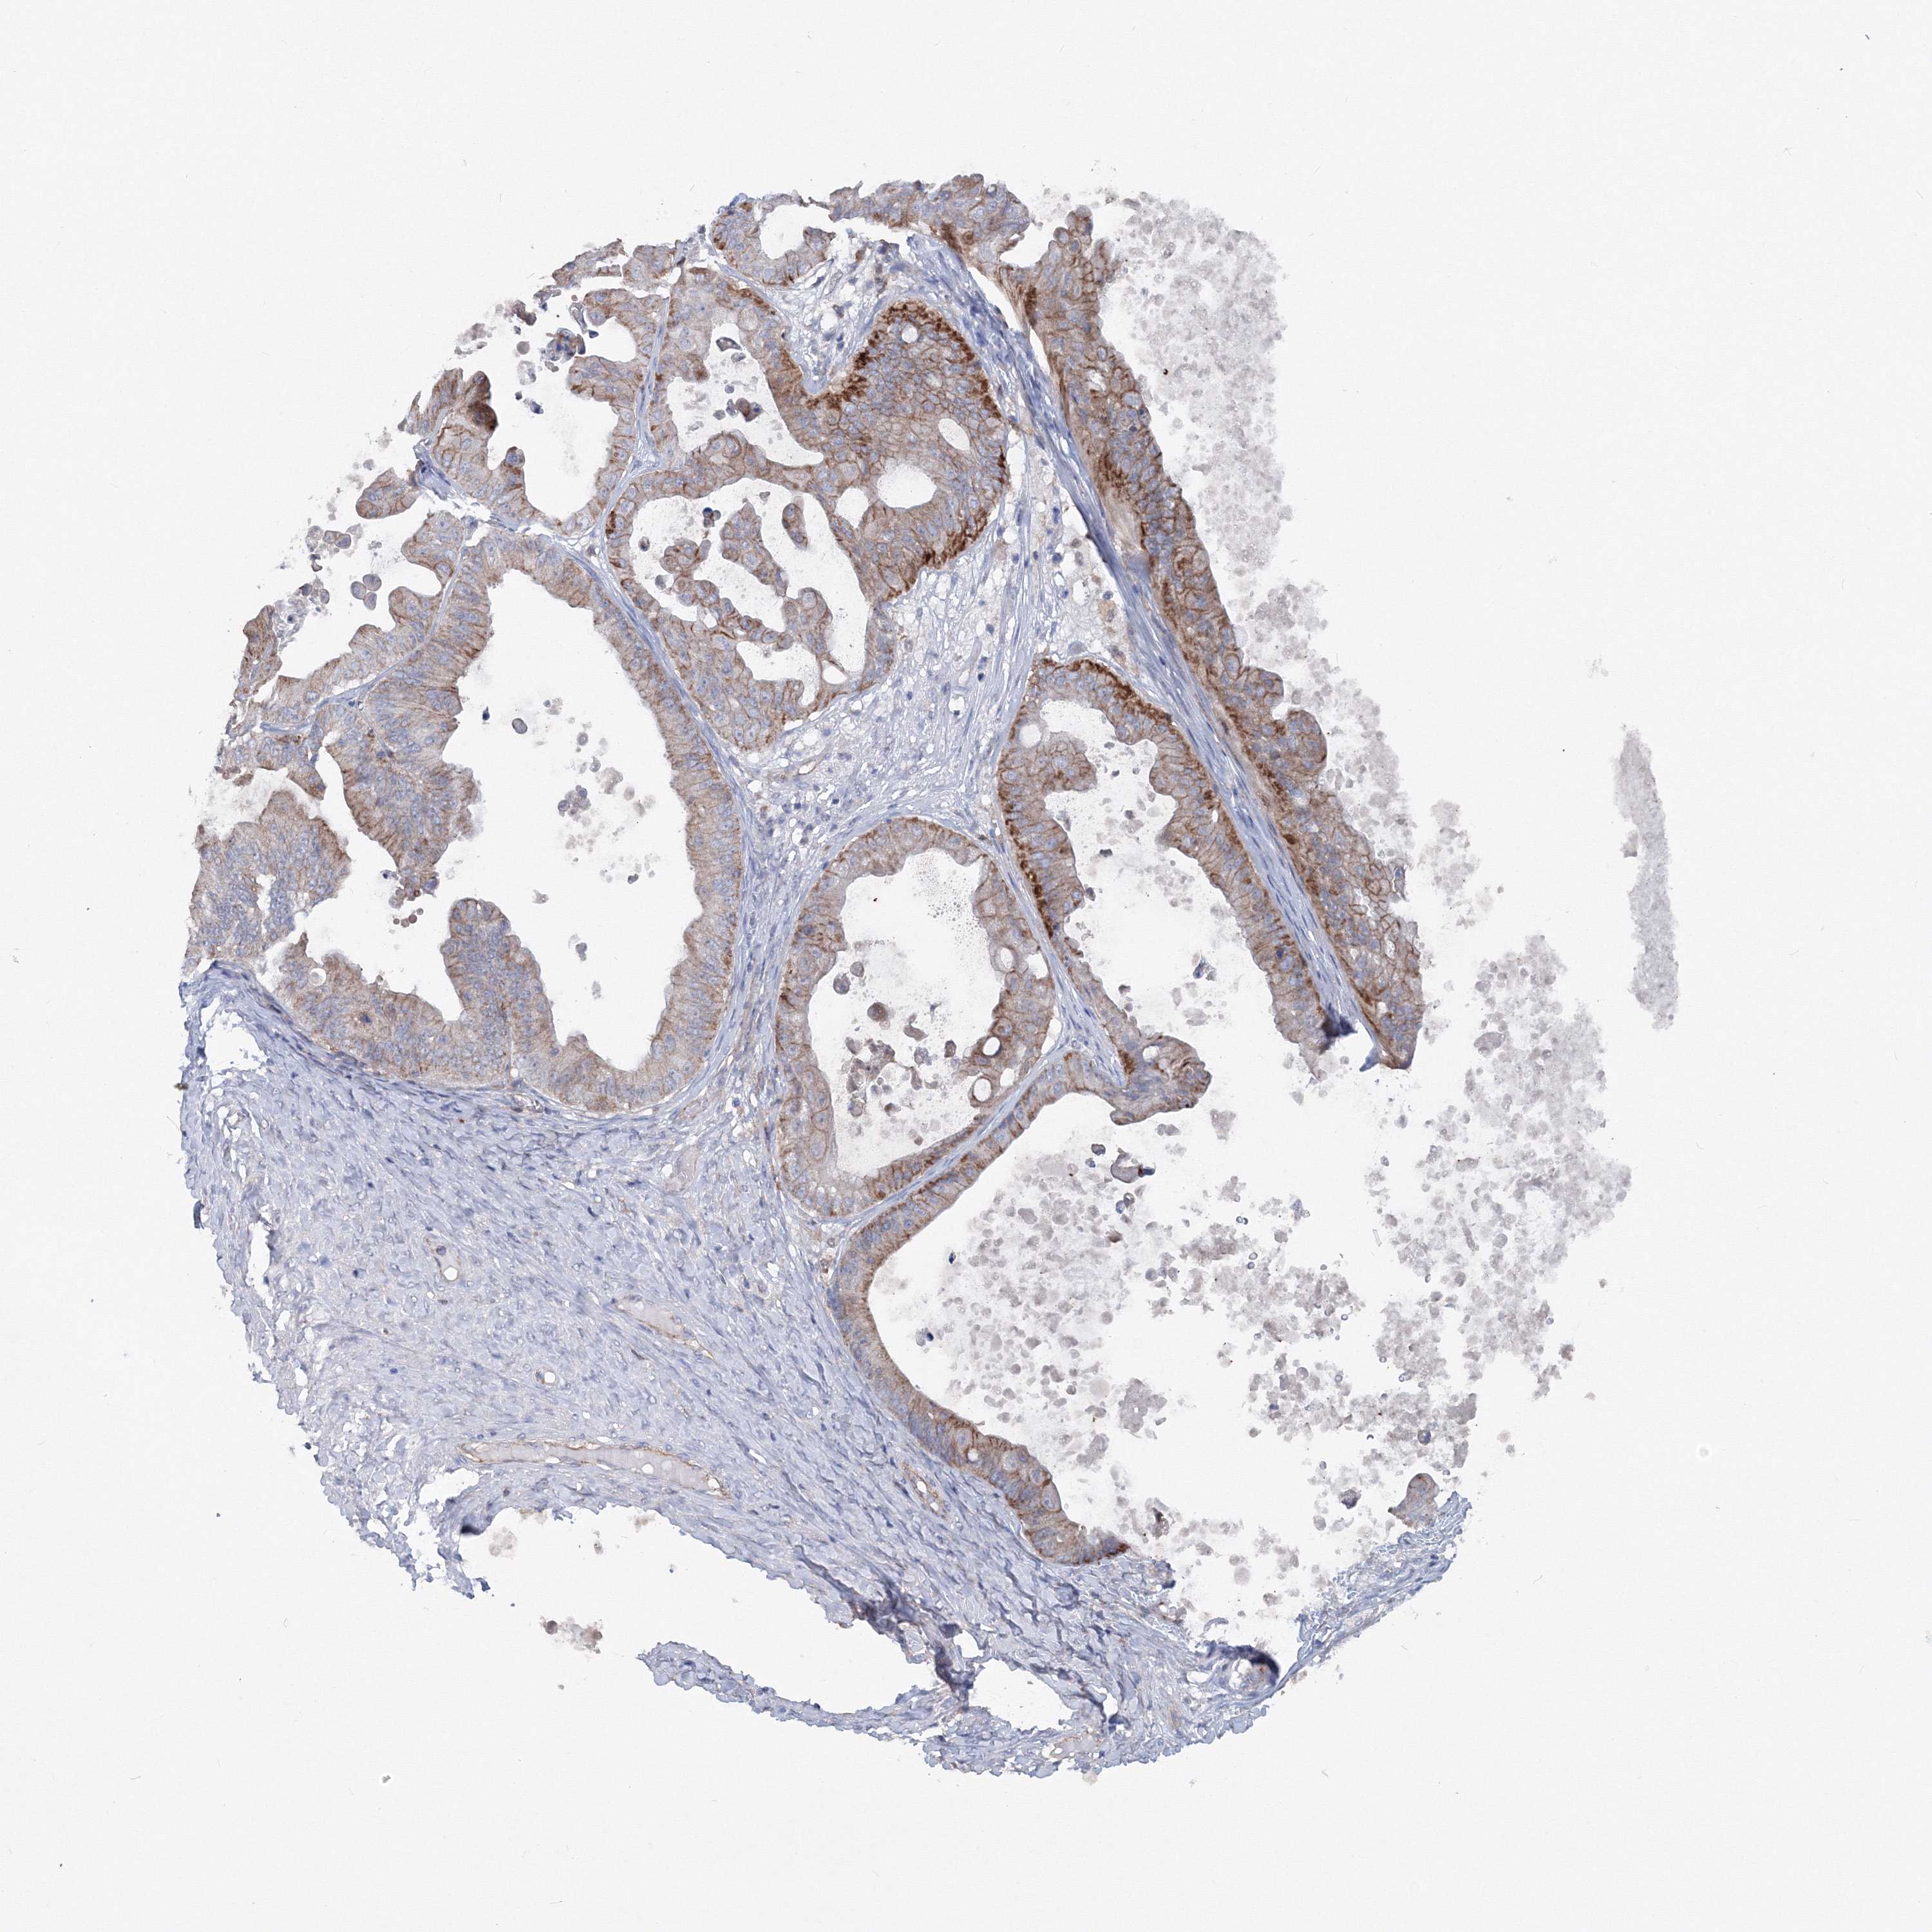

OVARIAN CANCER - Protein expressioni

A mouse-over function shows sample information and annotation data. Click on an image to view it in a full screen mode. Samples can be filtered based on level of antibody staining by selecting one or several of the following categories: high, medium, low and not detected. The assay and annotation is described here.

Note that samples used for immunohistochemistry by the Human Protein Atlas do not correspond to samples in the TCGA dataset.

Antibody stainingi

Antibody staining in the annotated cell types in the current human tissue is reported as not detected, low, medium, or high, based on conventional immunohistochemistry profiling in selected tissues. This score is based on the combination of the staining intensity and fraction of stained cells.

Each image is clickable and will lead to virtual microscopy that enables deeper exploration of all samples and also displays staining intensity scores, fraction scores and subcellular localization as well as patient and tissue information for each sample.

Antibody CAB034422

Staining

High

Medium

Low

Not detected

Intensity

Strong

Moderate

Weak

Negative

Quantity

>75%

75%-25%

<25%

None

Location

Nuclear

Cytoplasmic/membranous

Cytoplasmic/membranous,nuclear

Cystadenocarcinoma, serous, NOS

Carcinoma, endometroid

Cystadenocarcinoma, mucinous, NOS

Carcinoma, NOS